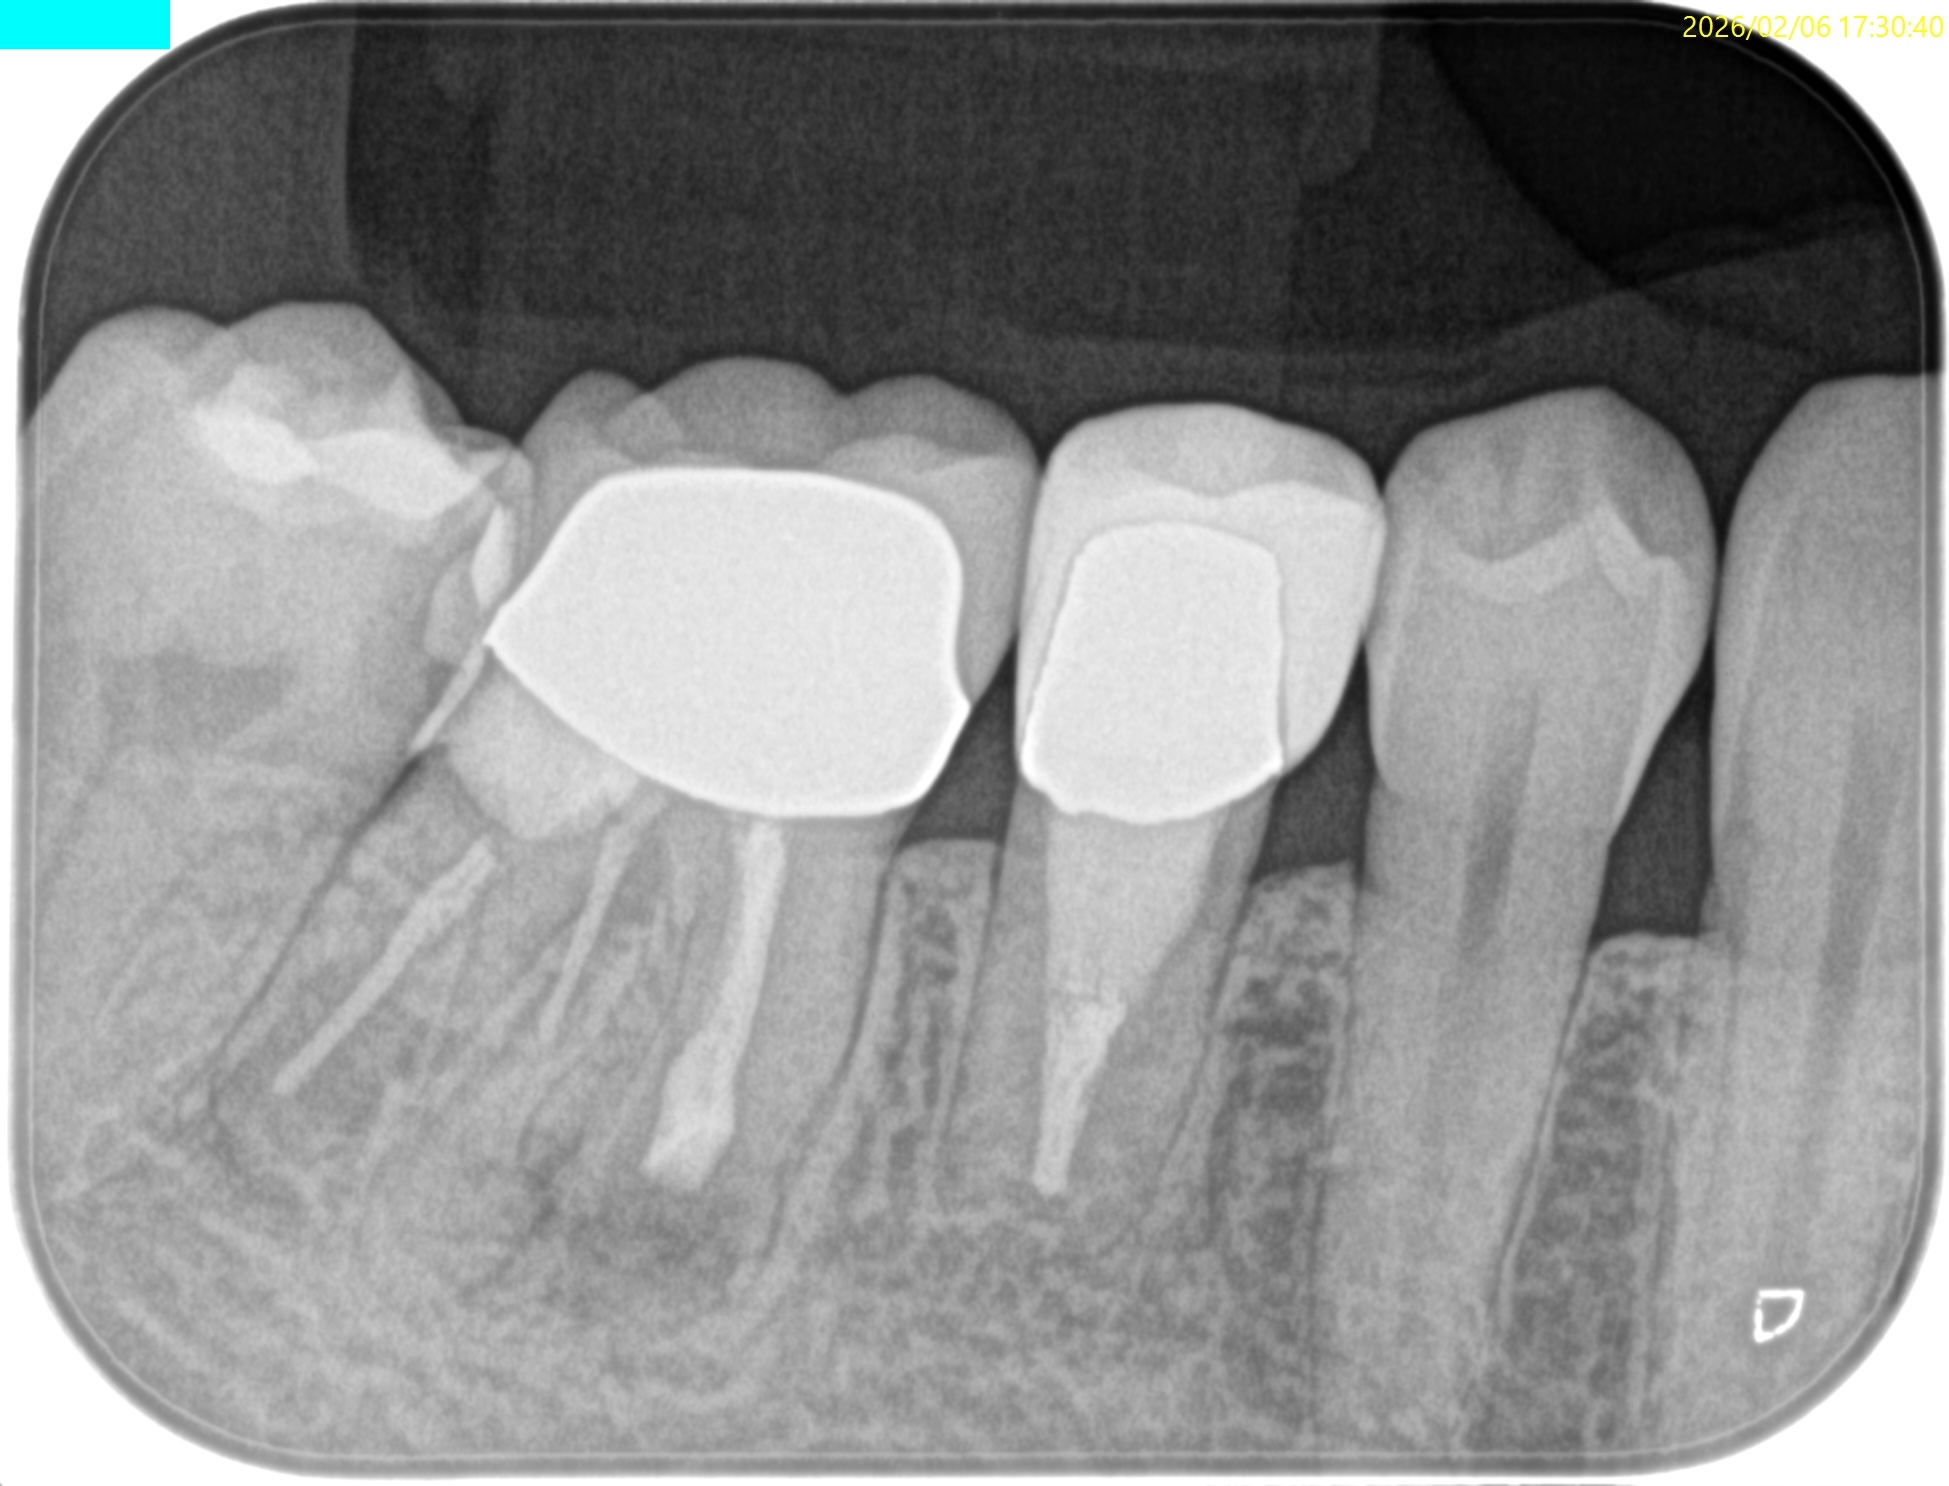

#30 M Apicoectomy 8M recall(2026.2.6)

骨欠損は完治していないが、検査で臨床症状が消失した点と、

術直後が、

骨欠損が今よりも大きく8ヶ月で縮小していることから問題はないと考える。

術直後と比較した。

完治ではないが大幅に問題が解決していることがわかる。